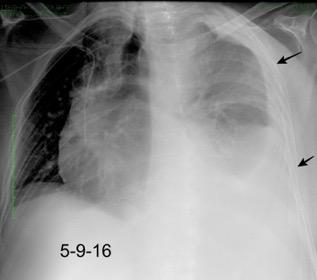

27. DERRAME PLEURAL IZQUIERDO. URINOMA

Hemorrágica………….30-70 UH

Urogénico……………….< 15 UH

Urinoma

Hemotórax